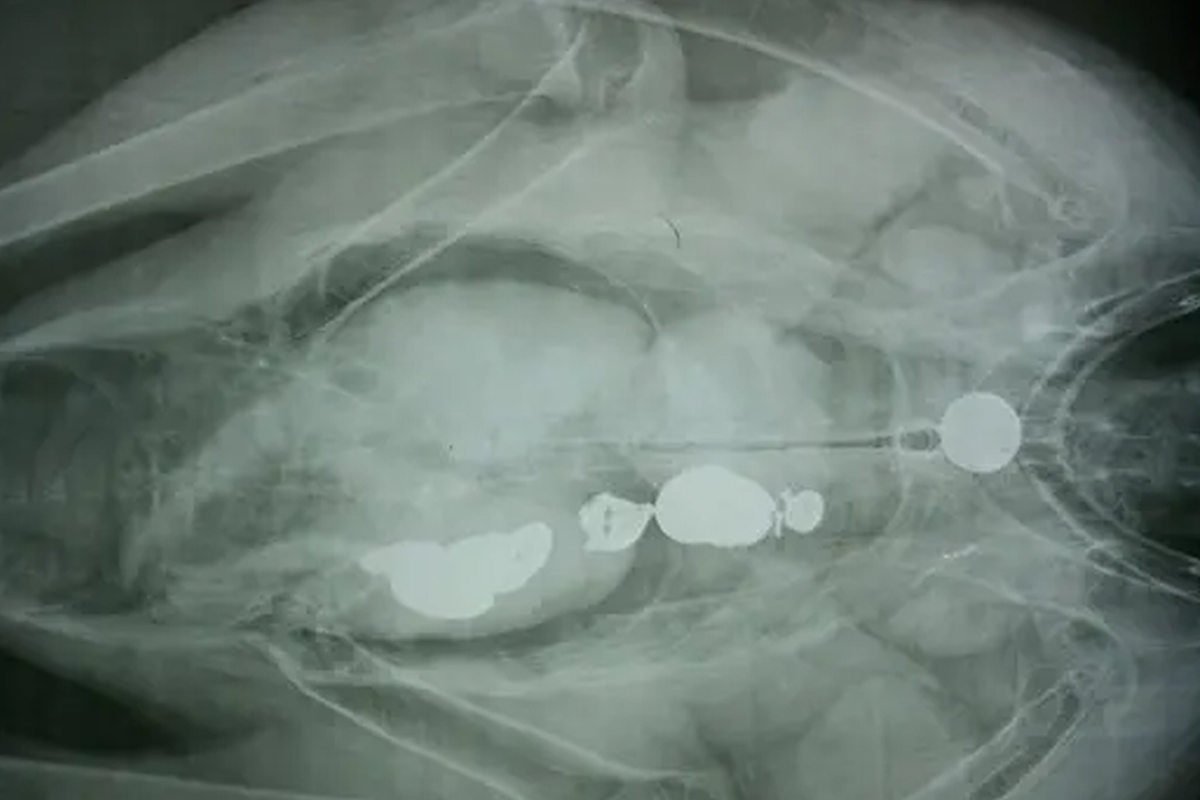

이들은 쓰레기 투기의 위험성을 알리고자 콘도르 뱃속을 촬영한 엑스(X)선 사진 결과를 공유하기도 했습니다. 해당 사진의 콘도르 몸속에는 관광객들이 던진 열쇠와 동전이 가득했죠.